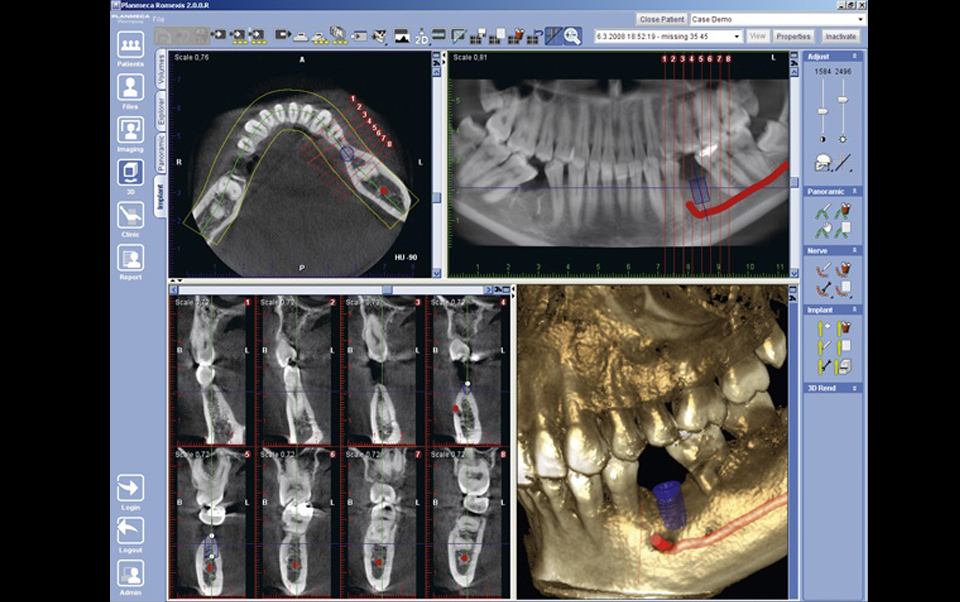

Los Tomógrafos Computados de Haz Cónico (Cone Beam Computed Tomography; CBCT) fueron específicamente diseñados para la obtención de información tridimensional del esqueleto máxilo facial, que incluye los dientes y tejidos adyacentes con una considerable menor dosis efectiva de radiación en comparación a la tomografía computada convencional médica (CT).